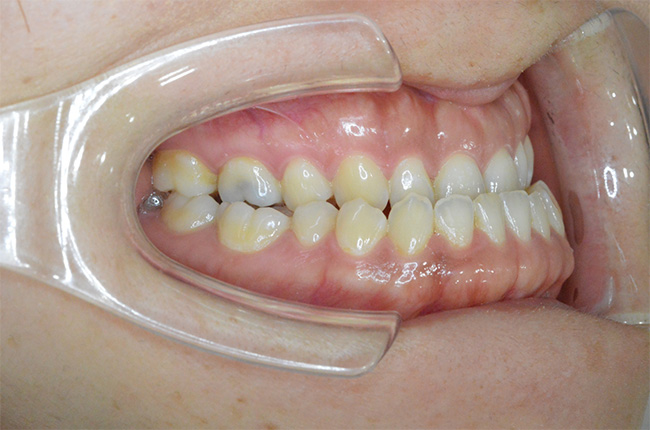

治療開始時

| 主訴 | 口元が出ている |

|---|---|

| 治療方法 | 上下顎小臼歯4本抜歯、ワイヤー矯正 |

| 治療内容 | 抜歯のスペースを使用して、上下前歯を後退させた |

| 治療期間 | 2年1ヵ月 |

| 治療費 | 979,000円(矯正装置・調整料・リテーナー・歯科矯正用アンカースクリュー・矯正治療後2年間経過観察料を含む) ※2025年10月以前の料金となります。 |

| 年齢 | 20代 |

| リスク・ 副作用 |

痛み、歯根吸収、歯肉退縮、虫歯、後戻り |